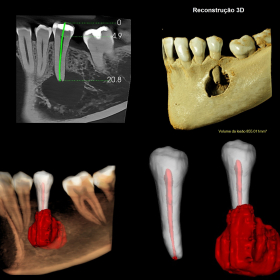

Laudos Tomográficos (TCFC): Planejamento para implantes, Avaliação de terceiros molares, Patologias ósseas e lesões bucais, Análise endodôntica, Avaliação das ATMs, Sinusopatias.

Segmentação e Arquivos Digitais: Segmentação endodôntica (STL) e cortes personalizados.